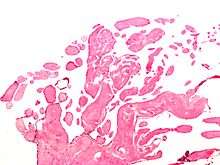

The diagnosis is confirmed by pathology. Histologically, papillary fibroelastomas have branching avascular papillae, composed of collagen, that are covered by endothelium.